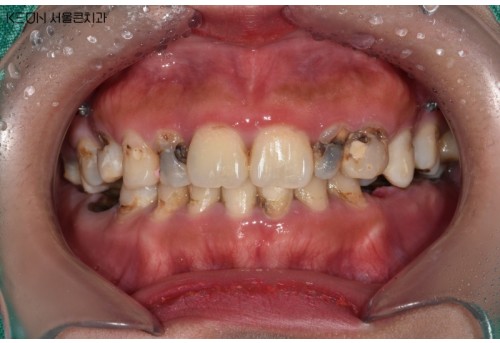

충치치료

1 치과공포증 치료 케이스

안녕하세요.대표원장 손승환 입니다.오랫만에 블로그 글로 인사드리는 것 같네요.요근래 환자분들이 많이 찾아주셔서 너무 정신없..